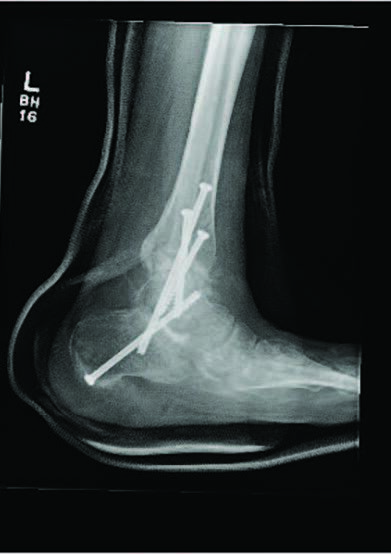

There are several studied and suggested surgical fixation options for treating complicated diabetic ankle fractures. As mentioned earlier, inappropriate treatment of these injuries can often lead to complications including the worst case scenario of Charcot arthropathy, and potential resultant limb loss. Hence, the common fundamental goals currently used for Charcot reconstruction also apply in ankle fracture fixation for patients with complicated diabetes.7 Specifically, these include obtaining a fixation construct with maximum rigidity and absolute stability, extending the fixation beyond the immediate zone of injury and planning incisions to minimize soft tissue trauma and optimize healing.4 Some fixation constructs suggested in recent literature include: circular external frame fixation; internal fixation using screws and plates; tibiotalocalcaneal (TTC) nail construct; and even locked fibular intramedullary nail fixation.4,8-10

Alternately, the TTC nail allows a minimally invasive approach to a robust and rigid construct. A retrospective case series by Ebaugh and colleagues looked at 27 patients who underwent TTC nailing as a primary fixation method without joint preparation and followed them for an average of 2.5 years.8 Overall, their limb salvage rate was 96 percent, the mean time to weight bearing was 6.7 weeks and their fracture union rate was 88 percent. Their surgical complication rate was 18.5 percent, but none of the complications included malunions, nonunions or development of Charcot arthropathy.8